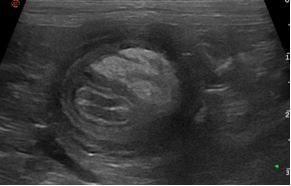

An advanced, highly practical ultrasound course designed to extend diagnostic capability, combining hands-on training in challenging abdominal structures, Doppler techniques and ultrasound-guided sampling for confident clinical application.

This course is suitable for you if you‘re a general practitioner who already has experience performing an abdominal ultrasound and would like to elevate your skills in evaluating the more challenging abdominal structures and at performing ultrasound-guided sampling. You’ll also learn how to use ultrasound for the assessment of the thorax (except heart) and neck, increasing the range of applications of this imaging modality that you can offer your patients. This two day Advanced Small Animal Ultrasound course will consist of a combination of lectures and several hands on practical sessions with the guidance of the course tutors.

- Become more proficient at identifying adrenal glands and pancreas, familiarising yourself with the different anatomical landmarks used to find these small organs and being able to differentiate normal appearance from pathological changes

- Identification of the major abdominal lymph nodes using the adequate anatomical landmarks and being able to differentiate normal appearance from pathological changes affecting these structures